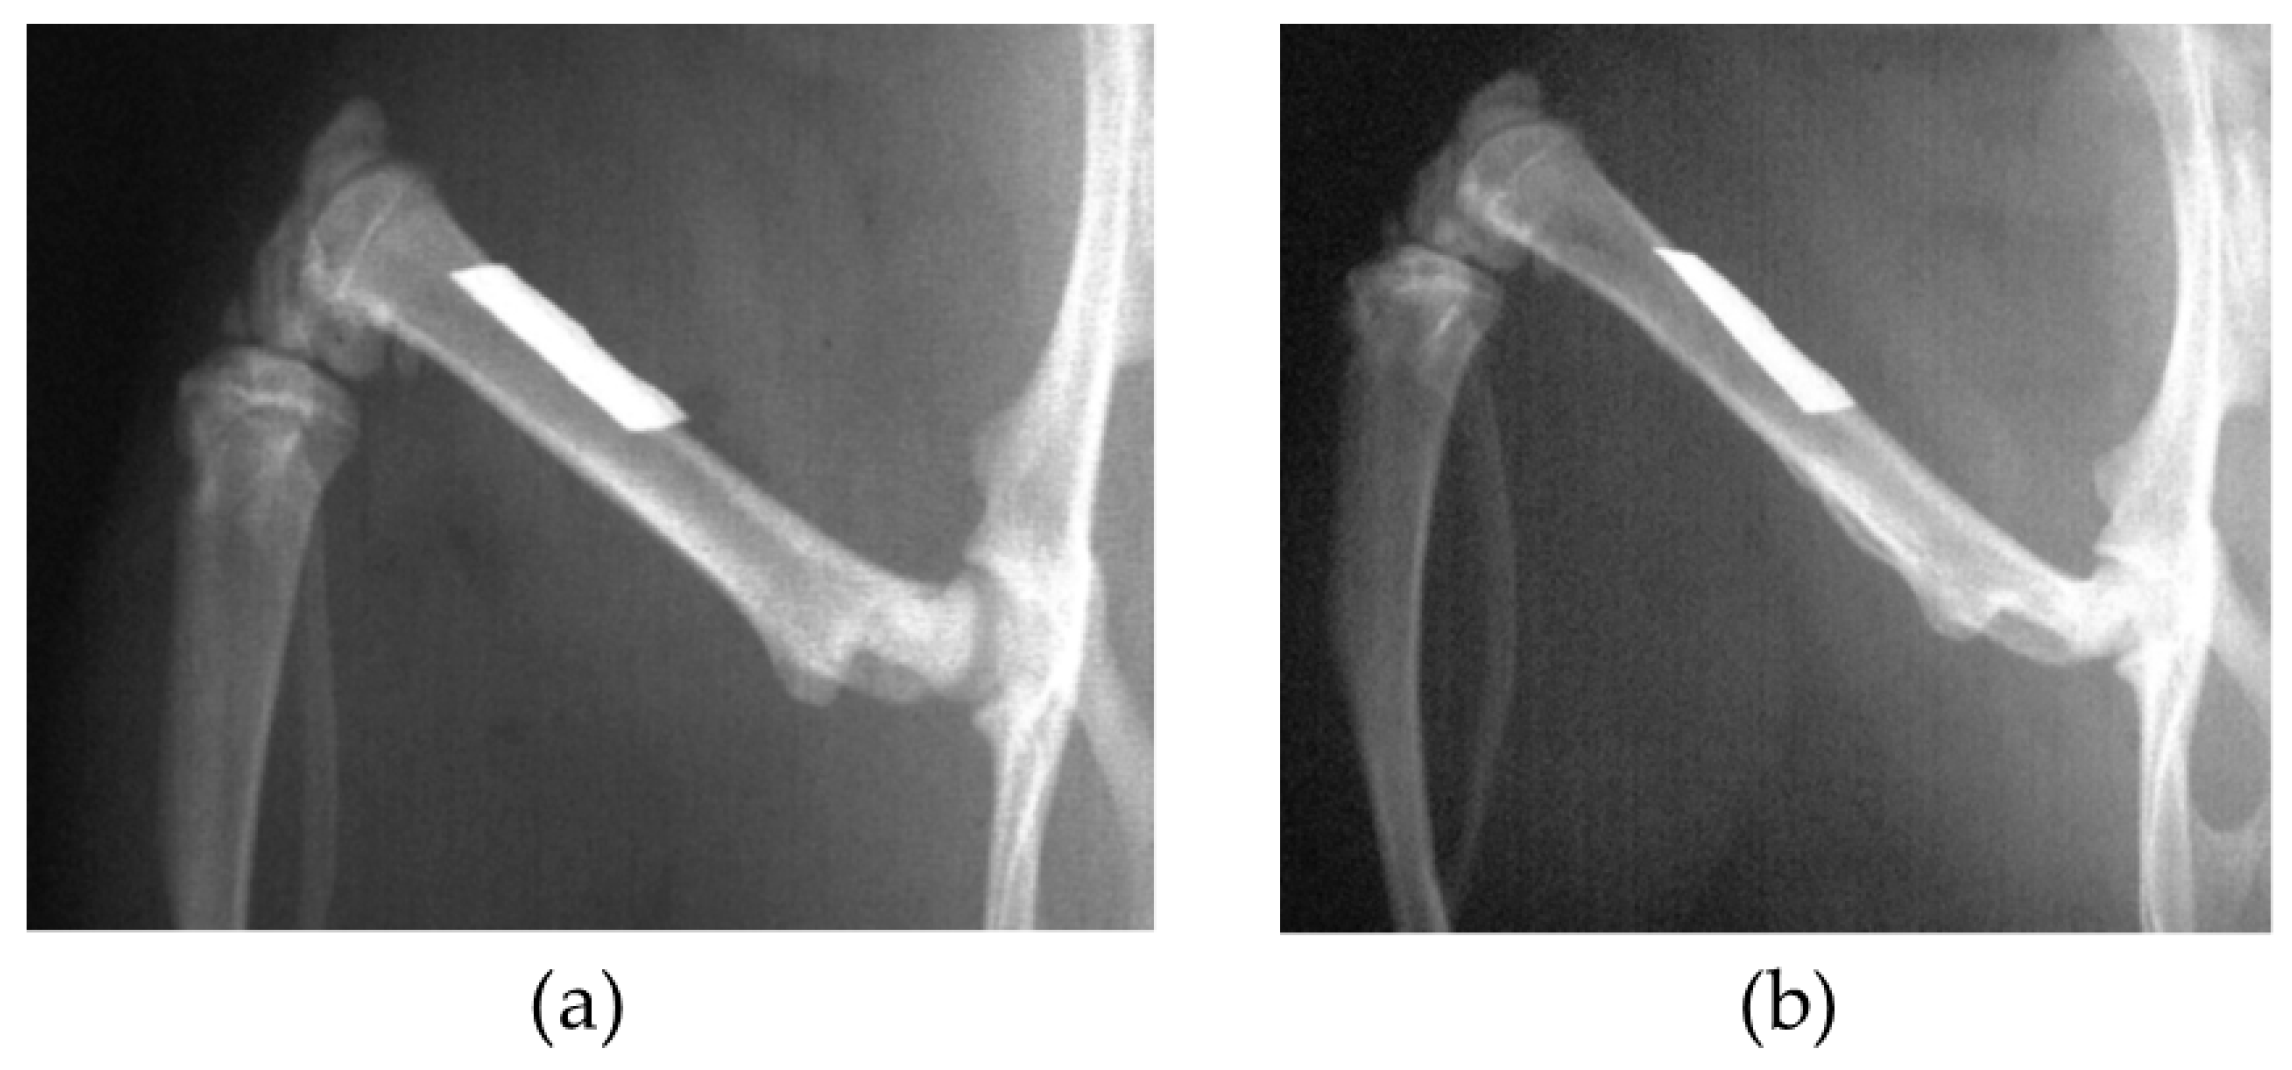

In the BMG nail group, the Ti-6Al-4V group, and the 316L group, osteotomy of left femoral bone was performed at 13 mm from the top of the greater trochanter using a fine-toothed circular saw. The medullary canal of the femoral bone was reamed using 1.5 mm and 2.0 mm diameter drill bits (Mathys Medical Ltd., Bettlach, Switzerland). After the reaming procedure, the nail was inserted from the trochanter to the femoral condyle, and the disconnected femoral bone was manually reduced (Figure 1). The contra-lateral right femoral bone in the BMG nail group, the Ti-6Al-4V group, and the 316L group was left intact.

Figure 1. Radiograph of left femoral bone just after osteotomy and BMG intramedullary nail implantation.

Figure 10. (a) Harvested femoral bone with BMG nail; (b) Radiograph of femoral bone and BMG nail at 12 weeks after osteotomy. The osteotomy sites were healed with callus formation (arrow).